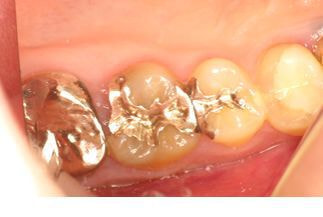

問診・視診・打診・温度診・レントゲンなどの検査を行っても原因が特定できない場合でも、マイクロスコープで検査を行うことで何が原因になっているか特定できる症例はたくさんあります。